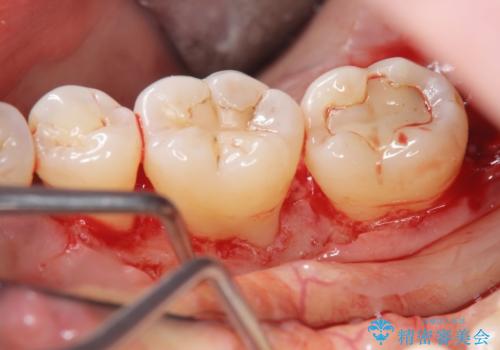

歯周病治療 → 歯槽骨の再生治療

骨を再生させて歯周病を治す 再生療法 50代男性

歯周病治療の注意事項(リスク・副作用など)

- 外科手術のため、術後に痛みや腫れ、違和感を伴います

- 歯周組織再生治療は患者様の状態によって術後の経過が異なります(見た目が改善しない場合もあります)